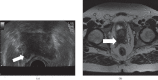

Transrectal ultrasound (TRUS) was first developed in the 1970s. TRUS-guided biopsy, under local anaesthetic and prophylactic antibiotics, is now the most widely accepted method to diagnose prostate cancer. However, the sensitivity and specificity of greyscale TRUS in the detection of prostate cancer is low. Prostate cancer most commonly appears as a hypoechoic focal lesion in the peripheral zone on TRUS but the appearances are variable with considerable overlap with benign lesions. Because of the low accuracy of greyscale TRUS, TRUS-guided biopsies have become established in the acquisition of systematic biopsies from standard locations. The number of systematic biopsies has increased over the years, with 10-12 cores currently accepted as the minimum standard. This article describes the technique of TRUS and biopsy and its complications. Novel modalities including contrast-enhanced modes and elastography as well as fusion techniques for increasing the sensitivity of TRUS-guided prostate-targeted biopsies are discussed along with their role in the diagnosis and management of prostate cancer.